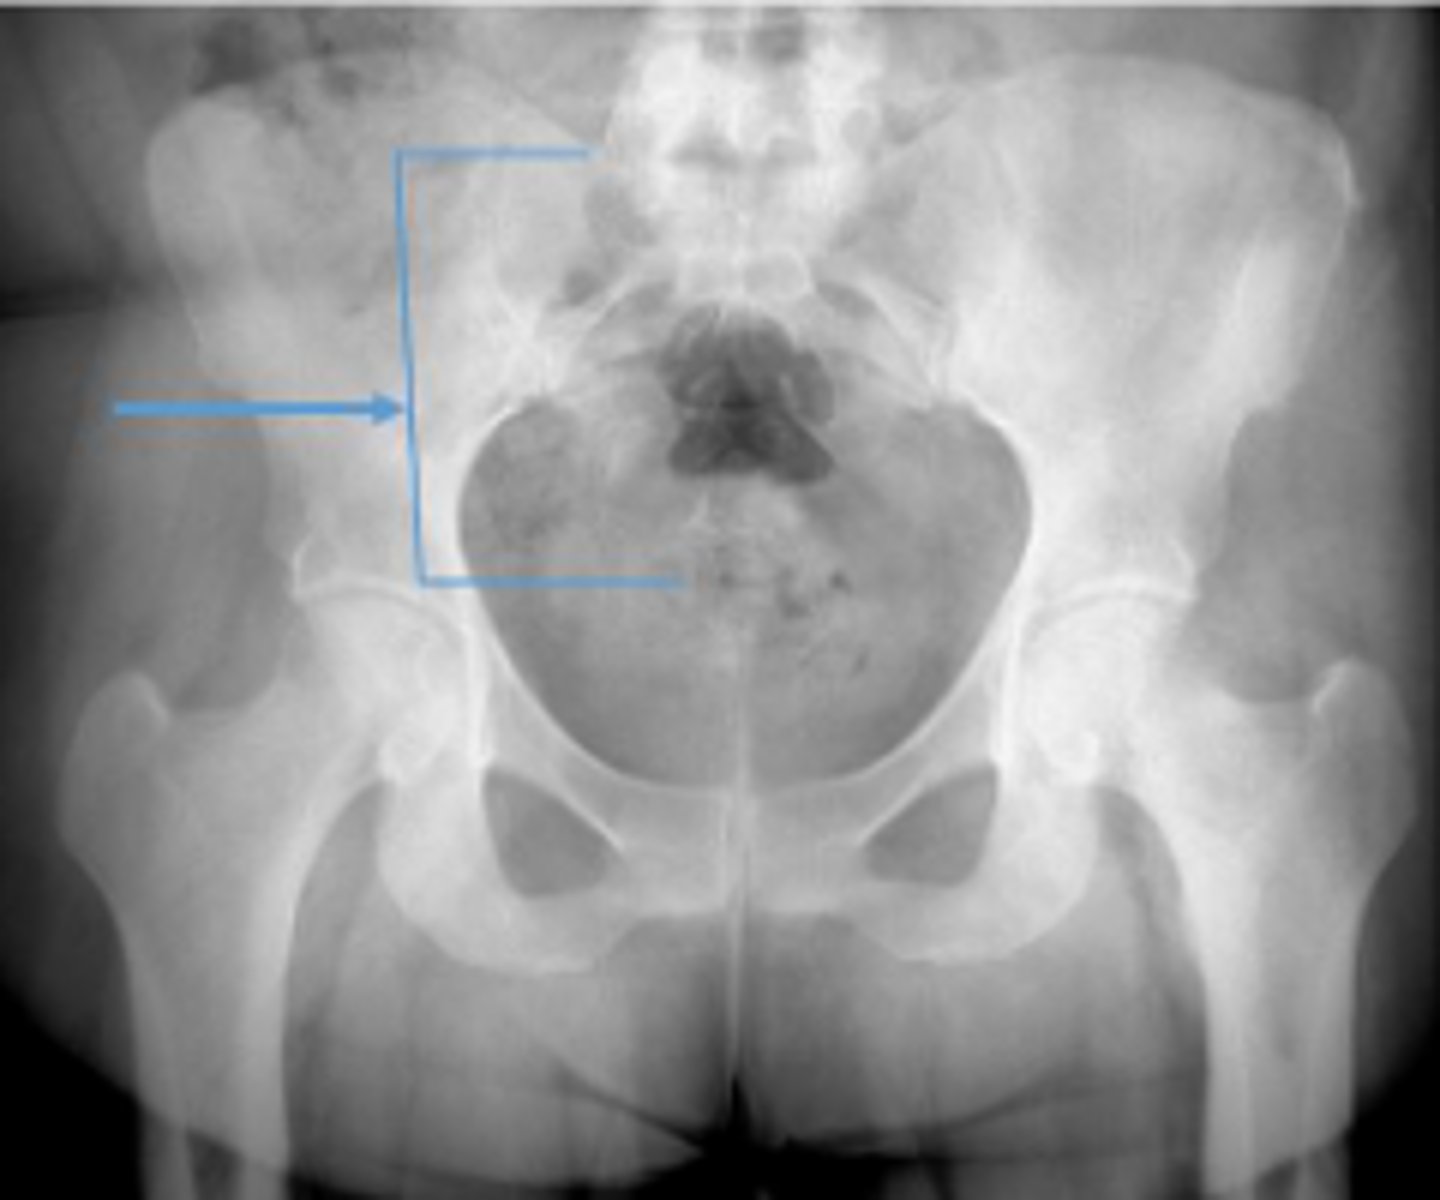

Posterior hip dislocation

What is most significant radiographic finding?

Shenton's line

What is the name of the assessment?

From the undersurface of the femoral neck

continued to the inferior aspect of the superior

pubic ramus

What are the osseous land marks for this assessment?

Hip dislocation, fracture

Name 2 conditions that may result in an abnormal assessment?